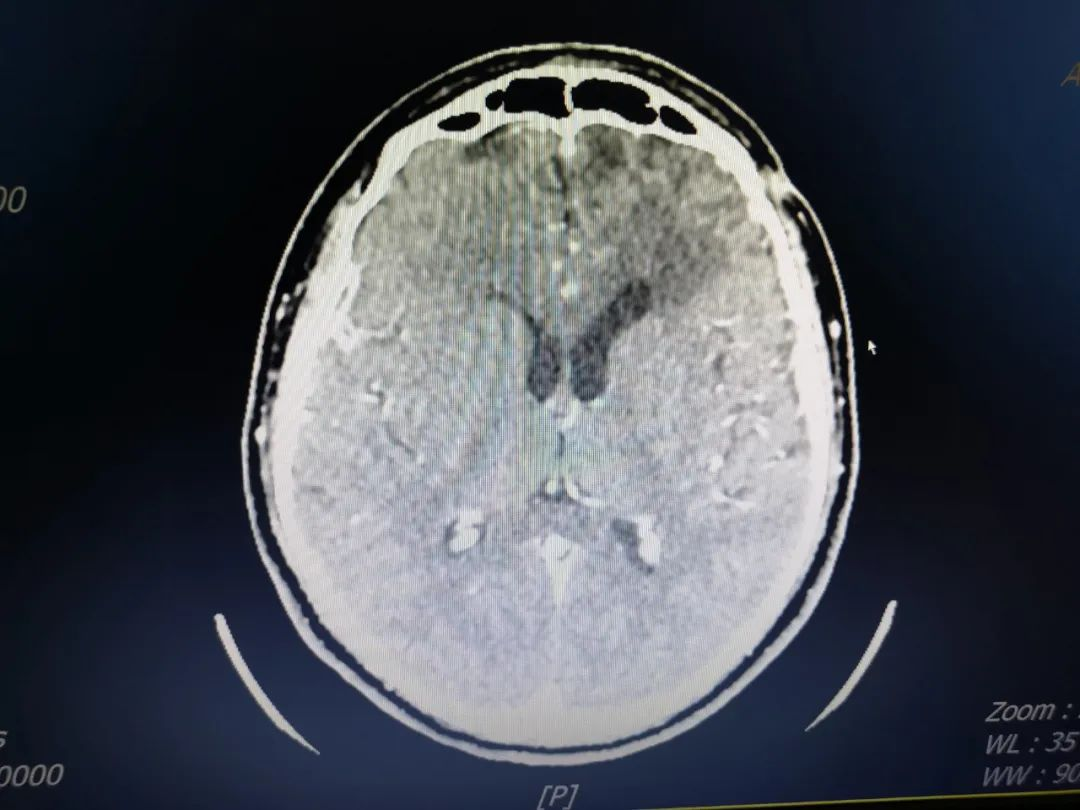

因腰大池引流患者需要卧床,神经外科一区护理团队每日需要细致地为患者翻身拍背、监测体温变化、根据引流液量调整引流管高度等,患者经历了剧烈头痛、寒颤、高热等一系列的临床症状后,病情逐渐好转,引流液渐渐由脓液变成清亮脑脊液,脑脊液常规检查各项指标恢复正常,脑脊液细菌培养无细茵生长。经过神经外科一区医护团队的精心照料,患者得以康复,患者家属也特地通过微信文字表达了感激。

术后CT增强示左额叶脓肿消失